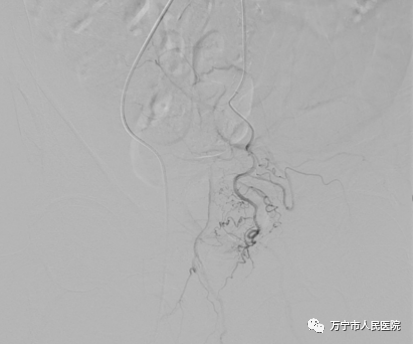

术中髂内动脉造影显示前列腺动脉开口隐蔽

医生耐心寻找前列腺动脉开口,并用微导管超选择插管成功